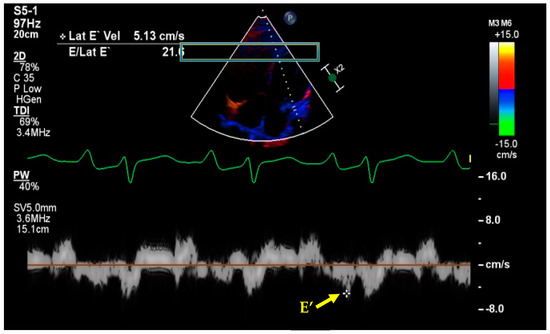

7. Basic and Advanced Echocardiography

- Kim, J.S.; Yang, J.W.; Yoo, J.S.; Choi, S.O.; Han, B.G. Association between E/e ratio and fluid overload in patients with predialysis chronic kidney disease. PLoS ONE 2017, 12, e0184764. [Google Scholar] [CrossRef] [PubMed]

- Nagueh, S.F.; Middleton, K.J.; Kopelen, H.A.; Zoghbi, W.A.; Quinones, M.A. Doppler tissue imaging: A noninvasive technique for evaluation of left ventricular relaxation and estimation of filling pressures. J. Am. Coll. Cardiol. 1997, 30, 1527–1533. [Google Scholar] [CrossRef]

- Nagueh, S.F.; Smiseth, O.A.; Appleton, C.P.; Byrd, B.F., 3rd; Dokainish, H.; Edvardsen, T.; Flachskampf, F.A.; Gillebert, T.C.; Klein, A.L.; Lancellotti, P.; et al. Recommendations for the Evaluation of Left Ventricular Diastolic Function by Echocardiography: An Update from the American Society of Echocardiography and the European Association of Cardiovascular Imaging. J. Am. Soc. Echocardiogr. 2016, 29, 277–314. [Google Scholar] [CrossRef]

- Lanspa, M.J.; Gutsche, A.R.; Wilson, E.L.; Olsen, T.D.; Hirshberg, E.L.; Knox, D.B.; Brown, S.M.; Grissom, C.K. Application of a simplified definition of diastolic function in severe sepsis and septic shock. Crit. Care 2016, 20, 243. [Google Scholar] [CrossRef]

- La Via, L.; Dezio, V.; Santonocito, C.; Astuto, M.; Morelli, A.; Huang, S.; Vieillard-Baron, A.; Sanfilippo, F. Full and simplified assessment of left ventricular diastolic function in covid-19 patients admitted to ICU: Feasibility, incidence, and association with mortality. Echocardiography 2022, 39, 1391–1400. [Google Scholar] [CrossRef]

- Denault, A.Y.; Langevin, S.; Lessard, M.R.; Courval, J.F.; Desjardins, G. Transthoracic echocardiographic evaluation of the heart and great vessels. Can. J. Anaesth. 2018, 65, 449–472. [Google Scholar] [CrossRef]

- Arbo, J.E.; Maslove, D.M.; Beraud, A.S. Bedside assessment of right atrial pressure in critically ill septic patients using tissue Doppler ultrasonography. J. Crit. Care 2013, 28, e1111–e1115. [Google Scholar] [CrossRef]